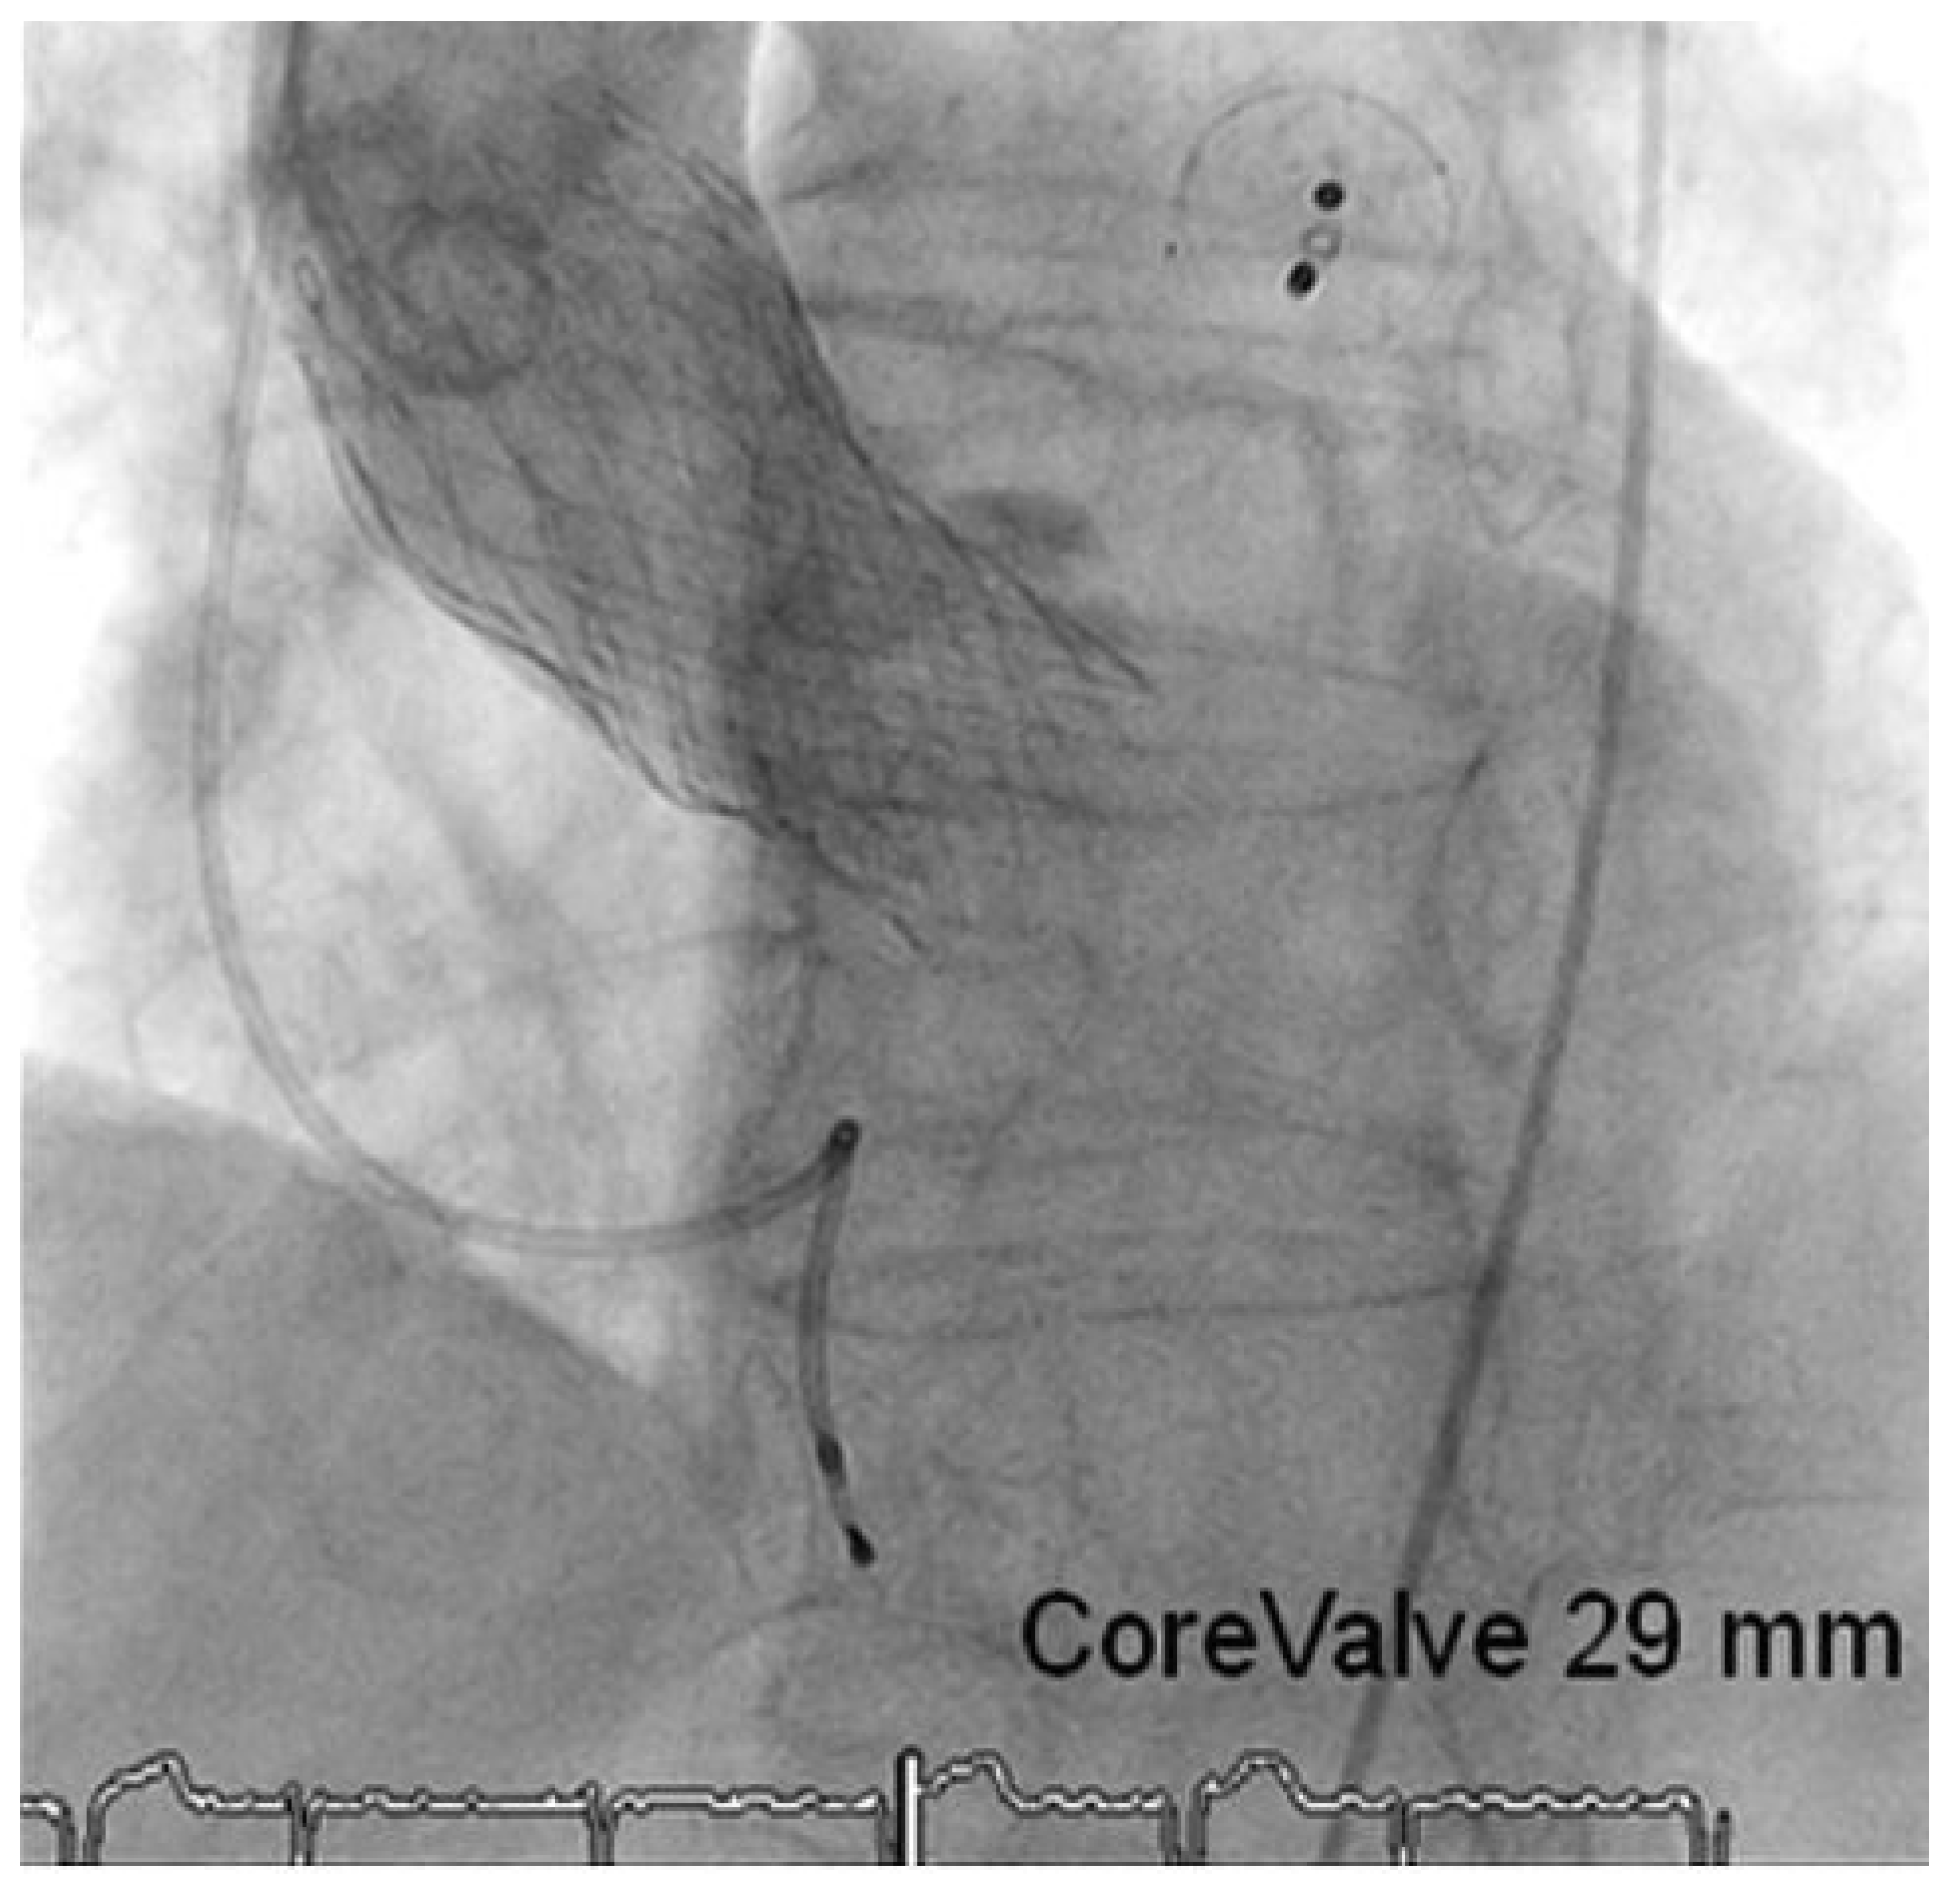

Through a transfemoral venous approach and transseptal puncture, the left atrial appendage was identified and an Amplatzer cardiac Plug 20 mm was positioned in the entry of the appendage. A stable position of the device and complete occlusion of the retroverted, single-lobulated appendage were verified by angiography before the device was released from the catheter (Figure 1 and Figure 2). Thereafter, coronary angiography was performed which showed significant stenosis of the mid left anterior descending coronary artery (LAD) and the proximal left circumflex coronary artery (LCX). Following successful treatment with two everolimus-eluting stents, respectively (Figure 3), angiography of the aorta and iliac artery was performed to measure the aortic valvar annulus and assess the peripheral access site. The patient qualified for implantation of a Medtronic CoreValve bioprosthesis and a 18 French sheath was introduced in the right femoral artery, as well as a temporary transvenous pacemaker through a right jugular access. After balloon dilatation of the degenerative aortic valve with a Nucleus balloon 25 × 40 mm under rapid pacing, the self-expandable bioprosthesis was deployed under fluoroscopic guidance (Figure 4). Periinterventional transoesophageal echocardiography demonstrated an excellent result with negligible paravalvular regurgitation. Simultaneous invasive measurement demonstrated a decrease in the mean transvalvular pressure gradient from 56 to 5 mm Hg. Closure of the right femoral access site was performed under temporary balloon occlusion of the right external iliac artery, from a contralateral femoral access with a Prostar device. The intervention was performed under general anaesthesia.

Figure 4. Concomitant LAA closure, double vessel revascularisation and aortic valve implantation.